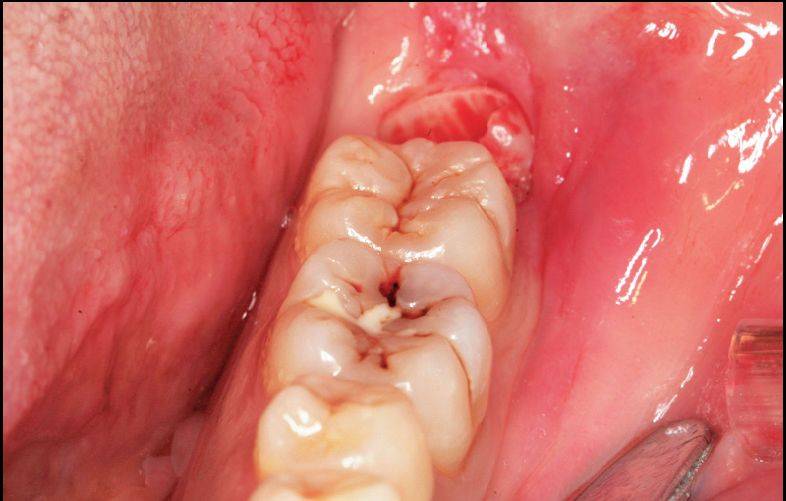

如下面的一个阻生智齿,可有三种拔除方法:

①劈开法:切开、翻瓣、去骨(凿)、劈开、挺除;

②钻拔法:切开翻瓣、去骨(钻)、分牙、挺;

③直接分牙拔除法:分牙拔除法(潜钻),可不切开、不翻瓣、不去骨拔除。

A.水平智齿仅露出远中牙冠

B.X线显示阻生智齿水平中位

C.直接分牙法并未切开、翻瓣、去骨拔除

D.智齿拔除,牙槽窝完好

同样的阻生智齿的不同拔除方法